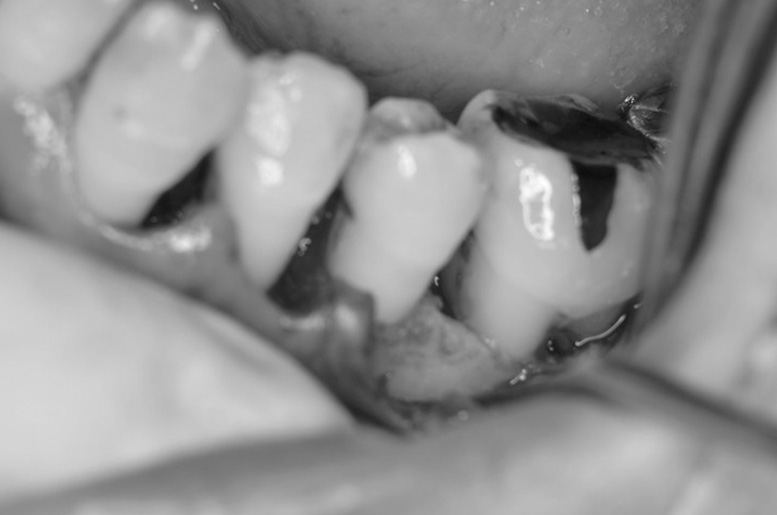

歯周再生療法 精密根管治療 歯周矯正治療 ジルコニアセラミック治療